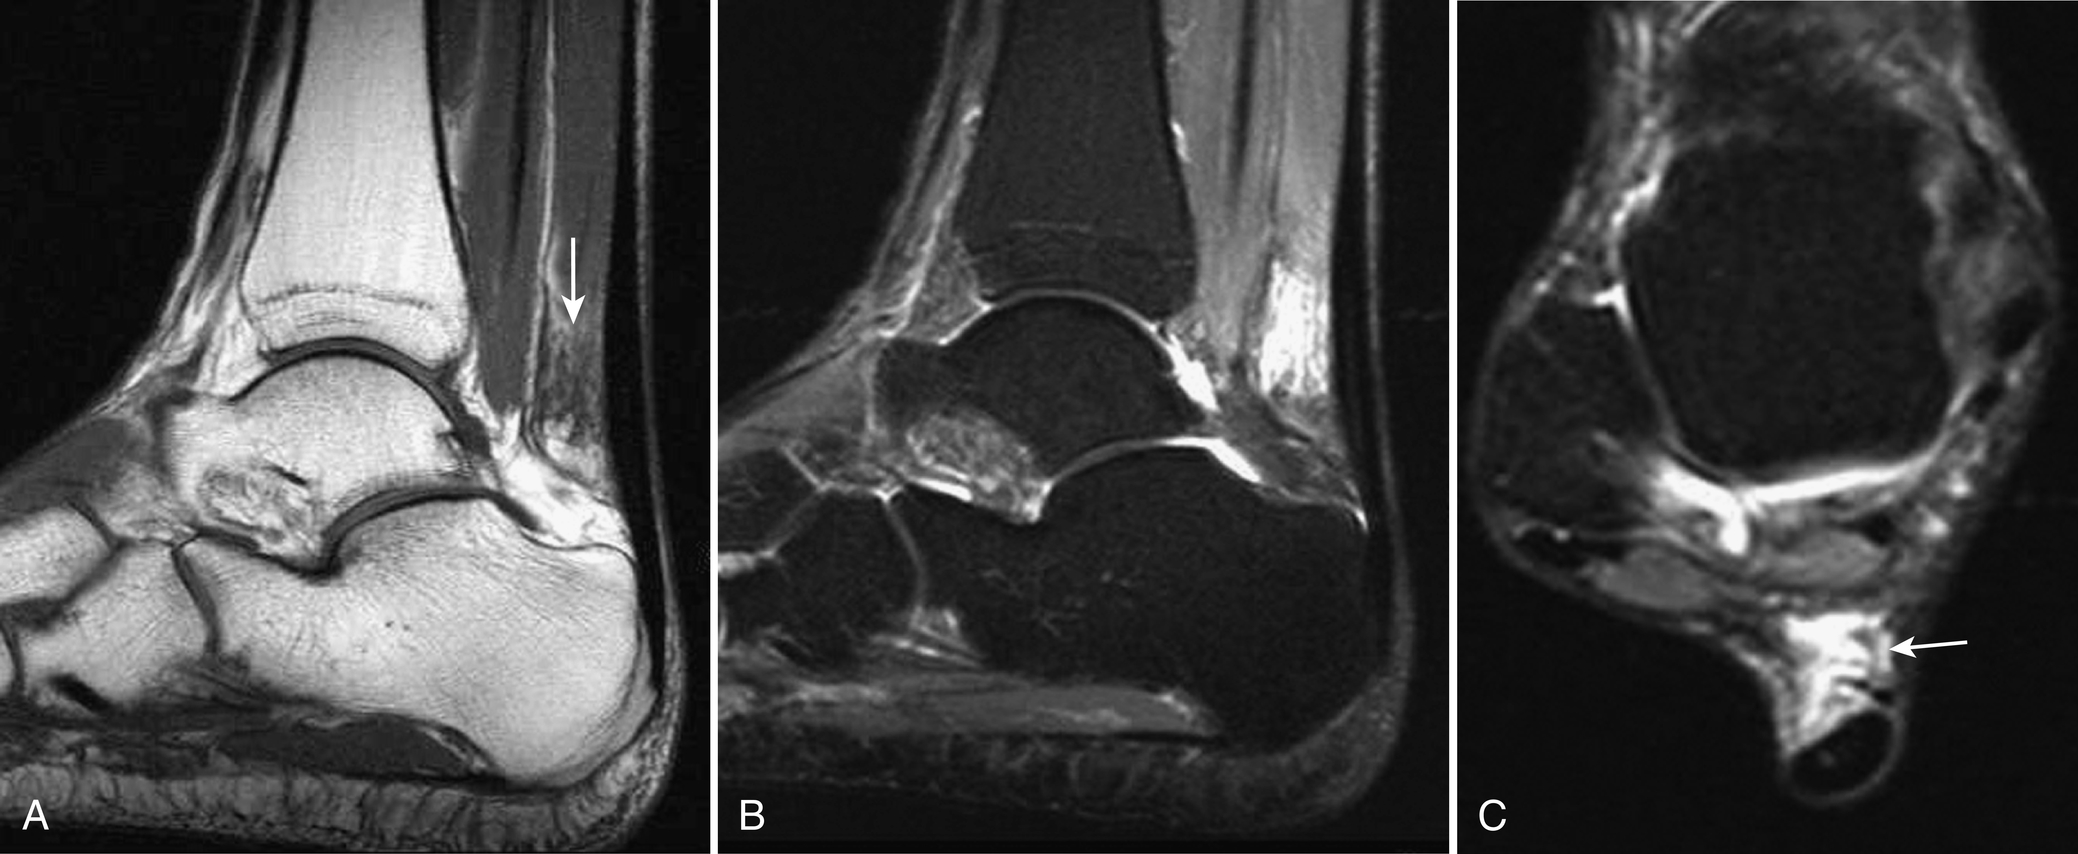

MRI of tenosynovitis shows a round collection of fluid that is low signal intensity on T1W and high signal intensity on T2W images, completely surrounding a tendon on images obtained transversely through it. The mesotendon may be identified as a thin, low signal intensity line extending from the tendon to the outer layer of the tendon sheath ( Fig. 3.5 ). The underlying tendon may be normal or abnormal in signal intensity and caliber. Stenosing tenosynovitis can be diagnosed on MRI by the presence of focal distention of a tendon sheath with fluid and thin, linear low signal intensity septations that course through the fluid in the sheath ( Fig. 3.6 ).

Fig. 3.5, Tenosynovitis.

Fig. 3.6, Stenosing tenosynovitis.